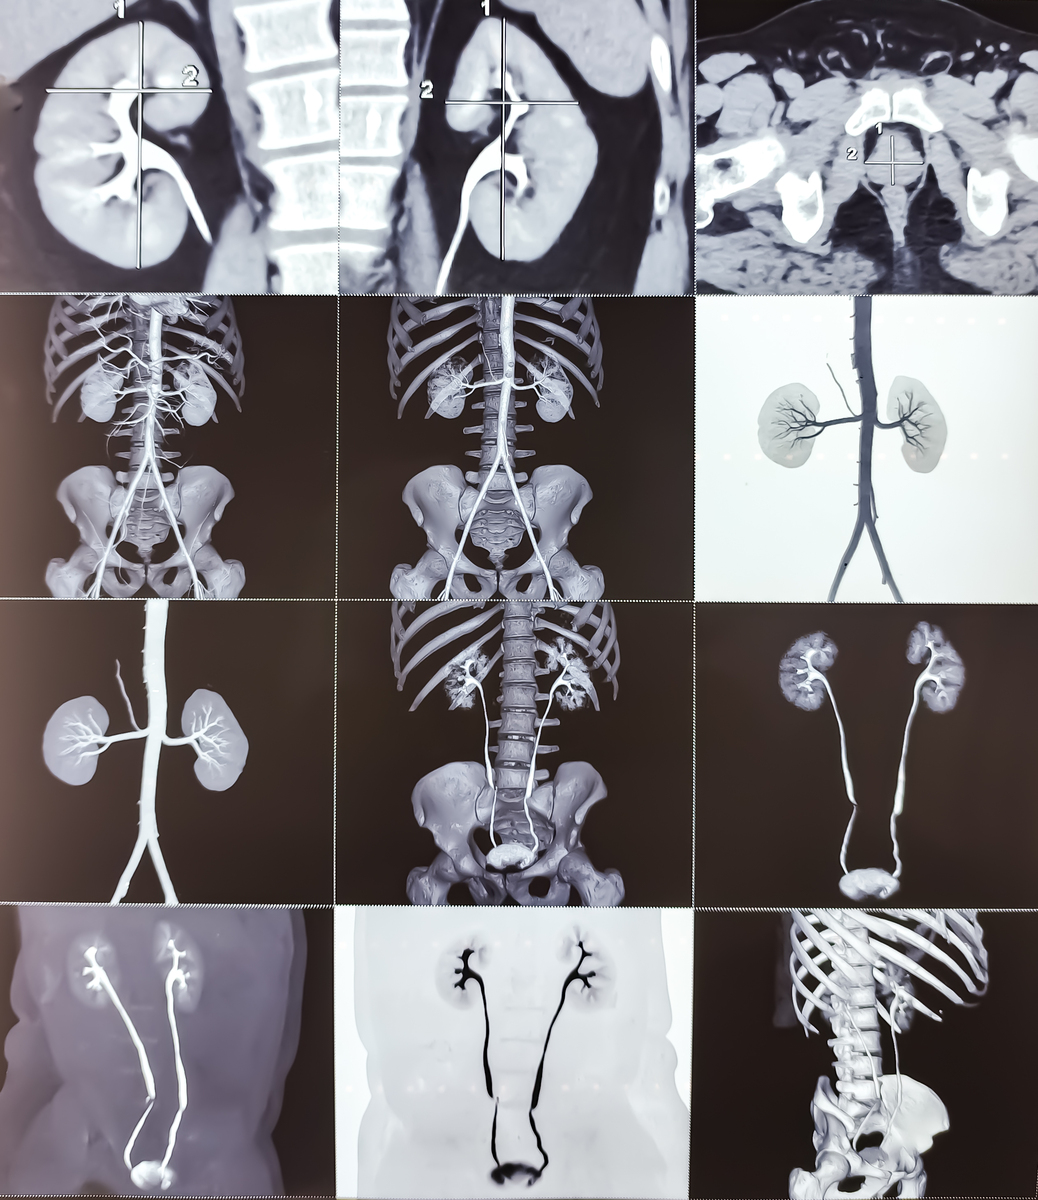

计算机断层成像技术(CT)是一种医疗成像技术,可以通过使用X射线和计算机算法来生成人体内部的三维图像。CT扫描可以探测身体内部的组织结构和器官,可以用于诊断和治疗各种疾病。

CT扫描使用的X射线是一种高能量电磁波,它可以穿透人体内部的组织,不同组织对X射线的吸收程度不同,这样就可以生成不同的强度图像。计算机算法将这些图像合成为一个三维图像,可以在不同方向上查看人体内部的结构。

CT扫描可以用于检查头部、胸部、腹部、盆腔和四肢等部位的组织和器官。它可以检测出肿瘤、骨折、血管疾病、肺炎、肝病、脑卒中等疾病,并可以指导手术和治疗计划。